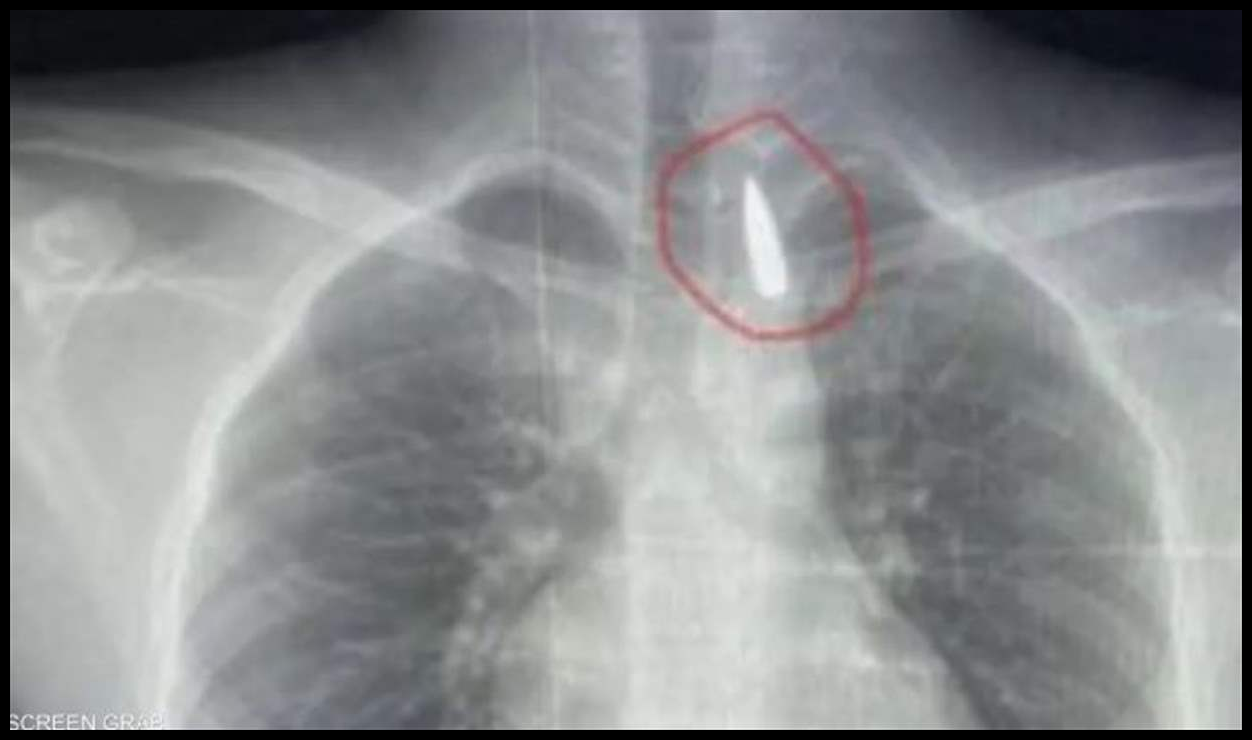

في جراحة نادرة ومعقدة.. أطباء مصريون بمشفى جامعة الإسكندرية يتمكنون من إزالة مقذوف استقر قرب الشريان الأورطي لطفل من غزة.

​الطفل تعرض لطلق ناري في الرأس فاخترق جسده واستقر المقذوف داخل تجويف القفص الصدري قرب الشريان الأورطي، أكبر وأهم شرايين الجسم والمسؤول عن تغذية جميع الأعضاء الحيوية بالجسم.